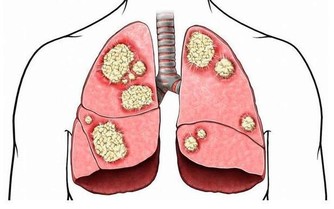

“一口兩口三口”,起初你並沒有發現什麼異常,但時間久了,寄生蟲吃的越來越多,胃受到的傷害越來越大,然後你就感到“胃疼”。往往感到胃疼的時候,胃已經千孔百瘡。而這個寄生蟲就是“幽門桿菌”。

幽門螺旋桿菌是目前發現在人胃中生存的唯一微生物,它的感染率高達50%至60% ,侵蝕胃粘膜,降低胃自我修復功能,有更多患有胃病的人出現。感染幽門螺旋桿菌患者,會出現以下典型的不適症狀!